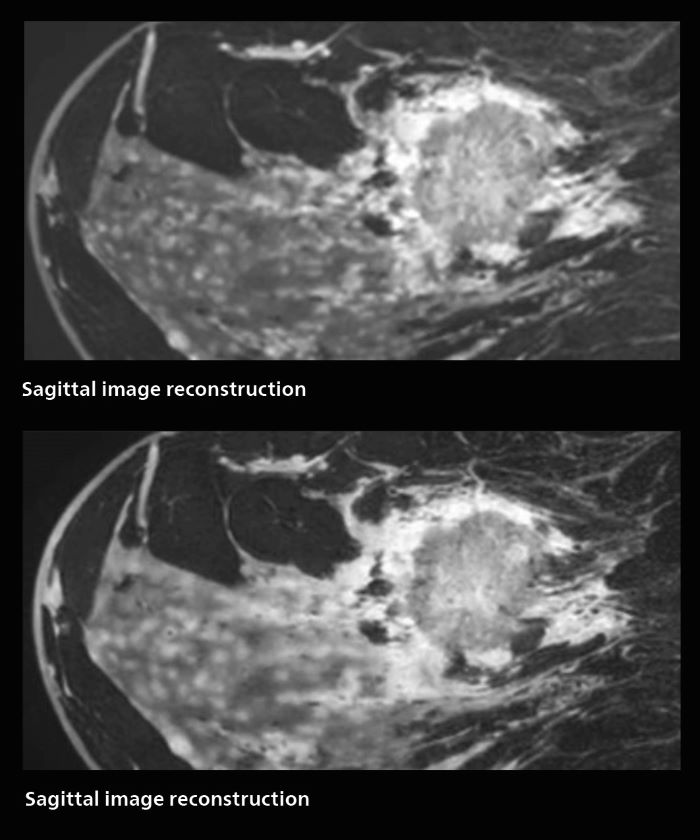

Speed and high image quality are also important factors determining the diagnostic value of breast MRI. “When the spatial resolution is not high enough for making the diagnosis of breast cancer, a very difficult decision must be made,” says Dr. Katahira. “Since SmartSpeed now allows us to increase the resolution, we can often easily provide a confident answer. In the past with SENSE we used 1.2 mm isotropic voxels in breast imaging after contrast admission. With Compressed SENSE that is 0.8 mm. Now with SmartSpeed we can acquire 0.6 mm isotropic voxels and the images are so clear that even tiny details are clearly visible.” “For example, we can now scan 20 consecutive, very fast dynamic images of the mammary glands with a single 3-second volume acquisition. This allows us to see how the blood flow is progressing in a very different way.” “The use of SmartSpeed has considerably improved our breast cancer imaging, with higher temporal resolution, higher spatial resolution, and higher SNR compared to the past, when we were using just Compressed SENSE. In addition, the dynamic study is now more useful in diagnosis because the ultrafast dynamic scan can be taken every 3 seconds.”

Scanning was performed with two different voxel sizes. AI enabled volume MRI allows image reconstruction in other directions. Biopsy revealed invasive ductal carcinoma in this patient. Performed on Elition X.